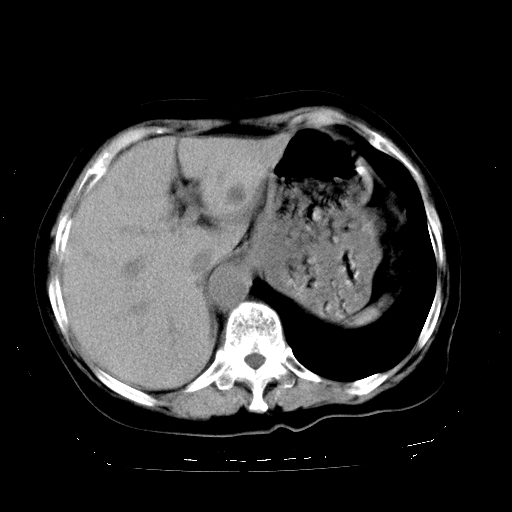

女,72岁,咳嗽、憋气一周,十年前曾患肺结核及胸膜结核。

1.右侧损毁肺伴胸膜钙化,2.左肺小结节灶,良性可能大,注意复查。3.肝脏左叶囊肿。4.先天性一侧肺不发育待出外(右侧胸廓无明显塌陷)。对比原片应该非常有帮助。